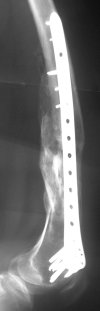

Attached are few examples from our Hospital:

B. Fixation loosening: distal cutting of the nail, non-unions do happen (cases attached).

Locking Plating has more distal screws than any nail, fixed angles and provides much better fixation, especially in osteoporotic bone.

Again, Locking Plating is minimally invasive, SUBCUTANEOUS INTERNAL FIXATION and I believe for the most surgeons preferred method of treatment for distal femur fractures (I do not have any financial interest with any of the manufacturers, parties).